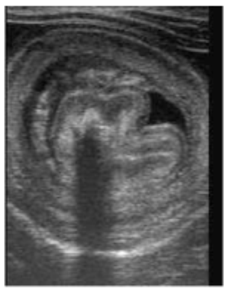

intussuseption